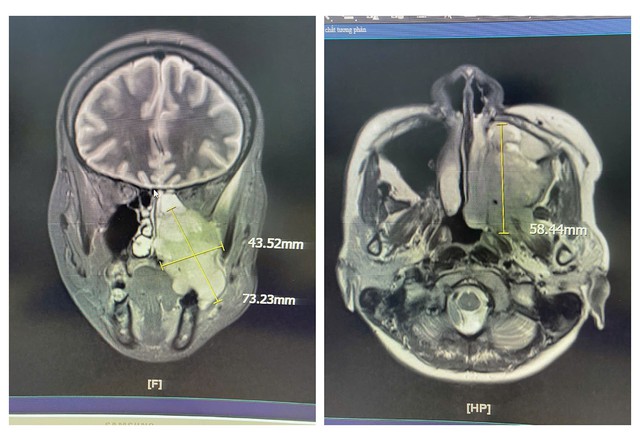

Các chẩn đoán hình ảnh bằng MRI, nội soi tai mũi họng cho thấy chị S. có khối u xuất phát từ xoang hàm - sàng trái, lan xuống khẩu cái, hố chân bướm hàm và vùng dưới thái dương trái. Kết quả sinh thiết mẫu mô từ hốc mũi và răng ghi nhận tổn thương phù hợp với Carcinoma tế bào gai không sừng hóa (ung thư).

Khối u với kích thước lớn có thể nhận thấy dễ dàng trên phim chụp cộng hưởng từ MRI